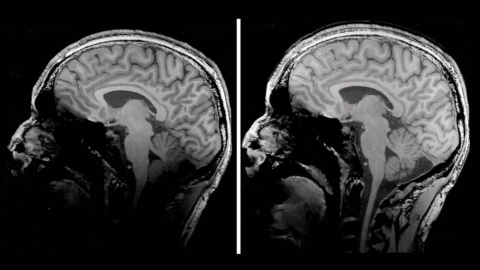

Magnetom Terra.X mit einer Feldstärke von 7T stellt den neuesten Stand der kommerziellen MR-Bildgebung dar. Das System wird der Nachfolger des 2017 eingeführten Magnetom Terra, dem ersten klinischen 7T-System, sein. Das höhere Signal bei 7T ermöglicht eine sehr hochauflösende Bildgebung, z.B. im Kopfbereich. Dies ist besonders wichtig bei Erkrankungen, bei denen der Nachweis kleinster Läsionen für die weitere Behandlung entscheidend sein kann. Auch im Knie kann die Sichtbarkeit kleinster Läsionen die Entscheidung für oder gegen eine Operation bedeuten. Die neue Hard- und Software von Magnetom Terra.X, die Siemens Healthineers „Ultra IQ Technologie“ nennt, wird die Möglichkeiten eines 7T Systems deutlich steigern: MR-Bildgebung bei diesen extrem hohen Feldstärken kann zu einer Verdunkelung des Bildeindrucks beispielsweise am unteren Teil des Kopfes führen. Mit Magnetom Terra.X sind potenziell relevante Befunde auch an den Bildrändern deutlich sichtbar. Während die klassische MRT-Bildgebung vor allem in Körperregionen mit viel Wasser im Gewebe funktioniert, lassen sich mit hohen Feldstärken auch andere Substanzen im Körper, wie zum Beispiel Natrium, besser darstellen. Diese Form der Bildgebung geht über die reine Darstellung der Anatomie hinaus und ermöglicht eine Visualisierung von Vorgängen im Körper wie dem Stoffwechsel.